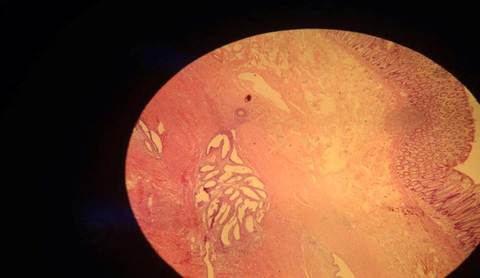

DIAGNÓSTICO. Fatores de risco. Gravidez Ectópica. DIP c/ salpingite crônica, aderências peritubárias, cirurgia prévia, DIU.

Qual é o achado obrigatório p/ diagnóstico da lesão. Vilosidades coriônicas revestidas por epitélio trofoblástico.